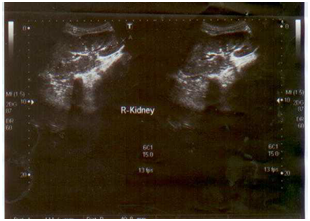

A 30-years old female was admitted to the National Medical Center with the history of persisting fever, headache, weakness, abdominal pain and loss of appetite since last 3 months. A week before arrival to the hospital, she was taking anti tuberculosis treatment (ATT), as prescribed by a local doctor without any actual diagnosis. The consultant after examining patient sent request for blood and urine culture, CBC, liver function tests, urea, creatinine, electrolytes, chest x-ray, ultrasound whole abdomen to the clinical laboratory and radiology department of the hospital respectively. Intravenous fluid infusion and panadol (to manage pain) were given initially to the patient until the investigation results revealed. The blood picture showed 7.9 g/dl (Hb), 424,000 mm3 (PLT) and 7,100 mm3 (WBC) respectively. The renal profile showed urea 10mg/dl and creatinine 0.5mg/dl while liver function tests were found to be within normal ranges. Chest x-ray showed no active lesion excluding pulmonary tuberculosis. The whole abdomen ultrasound showed normal liver, spleen, pancreas, gall bladder, urinary bladder, whereas the right kidney which was of normal size, shape and place. Figure 1A Echogenicity of renal cortex was seen as normal. Corticomedullary distinction was seen intact. But the left kidney was found enlarged (11.9 x 5.5) with perinephric abscess. There was well defined hypoechoic lesion of 6.5 x 3.6 cm noted in upper pole of left kidney extending outside the kidney and filled with thick level echoes inside. Doppler showed no significant flow (Figures 1B & 1C).

Figure 1A Ultrasound showing.

Figure 1B Normal right kidney.